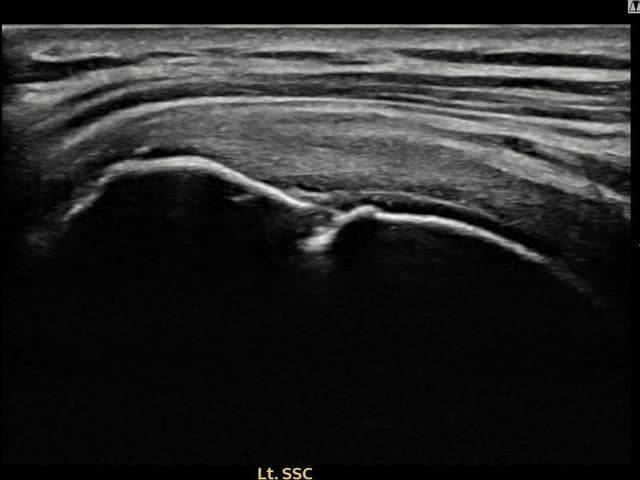

[촬영시기:24.01.08~24.03.14]

[어깨인대 축소봉합술] 좌측 어깨 통증으로 팔을 올리기 불편하여 내원하셨습니다.